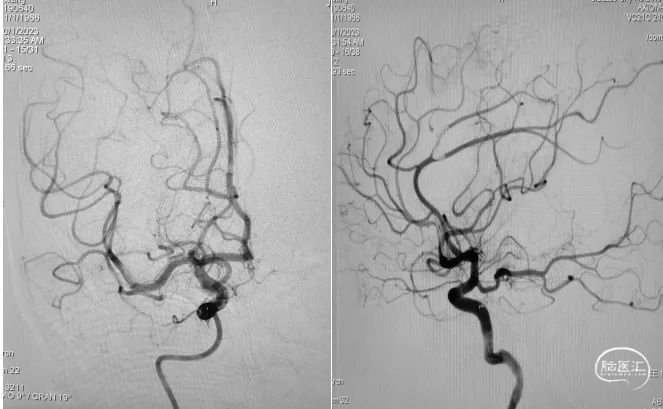

造影提示右侧大脑中动脉血流通畅。

取栓装置中可见白色胶冻状血栓。

6F心玮吞川®颅内血栓抽吸导管行基底动脉血栓抽吸。

复查造影示基底动脉及其分支显影良好,取栓装置中可见白色胶冻状血栓。

神志清楚,言语流利,双侧瞳孔等大等圆,直径3.0mm,对光反射灵敏,左侧鼻唇沟浅。左侧肢体肌力3级,右侧肢体肌力5级,双侧病理征阴性。感觉、共济查体未见异常,脑膜刺激征(-)。

NIHSS评分:5分。